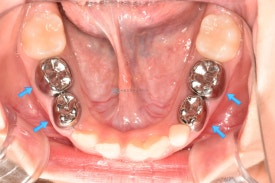

저희 병원에서 유치의 크라운을 할 때 치아색크라운(지르코니아 크라운)을 선택하시는 비율이 60퍼센트, 기존 은니(SS 크라운) 선택하시는 비율이 40퍼센트 정도 되는 것 같네요.

유치 지르코니아크라운은 높은 생체친화성, 은니와 비교할 수 없는 심미적인 우월성, 마모되지 않는 재질로 구멍이 날 걱정이 없다는 장점에도 불구하고, 그 시술의 까다로움 때문에 많은 치과의사들이 기피하곤 합니다.

유치지르코니아크라운과 은니 SS 크라운

하지만, 유치지르코니아크라운도 치아의 어느 포인트를 얼만큼 삭제해야하는지 정확히 알고 있다면 빠르게, 삭제량 크지 않게, 잇몸도 상하지 않게 한번에 잘 넣을 수 있습니다.

유치지르코니아크라운과 은니 SS 크라운하지만, 유치지르코니아크라운도 치아의 어느 포인트를 얼만큼 삭제해야하는지 정확히 알고 있다면 빠르게, 삭제량 크지 않게, 잇몸도 상하지 않게 한번에 잘 넣을 수 있습니다.